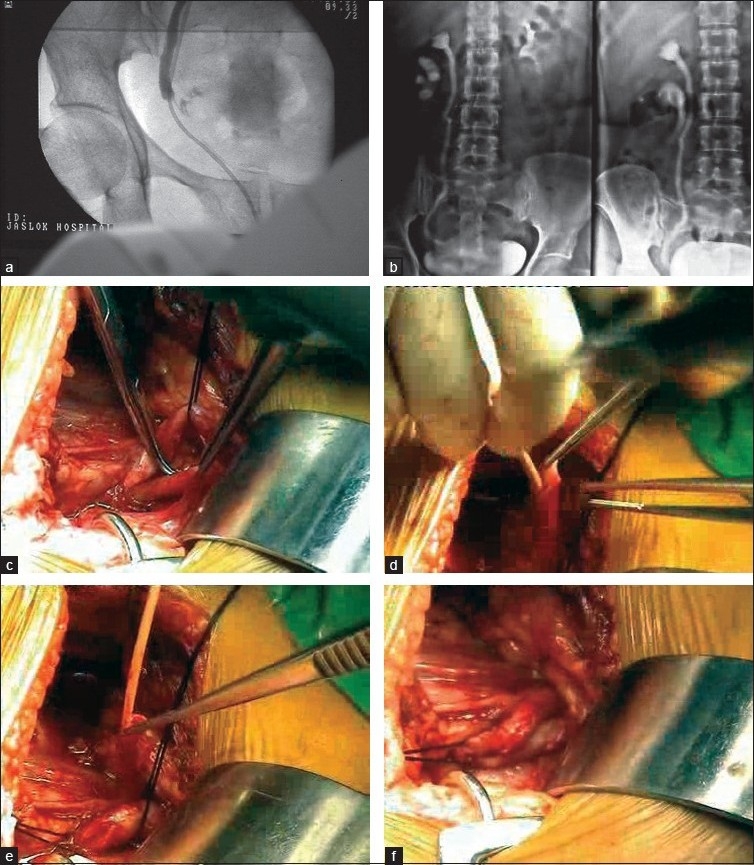

Objectives: To compare the risk of ureteric injury in total laparoscopic hysterectomy (TLH) using new vessel sealing devices (VSDs) and harmonic scalpel with simple scissors, bipolar and suturing. This was an evaluation of 1209 cases, carried out from May 1999 to April 2010.

Materials and methods: Out of 1209 patients, who had hysterectomies for various indications, TLH was done in 892 patients, 273 had vaginal hysterectomy and 44 had abdominal hysterectomy. We evaluated the incidence of ureteric injury in these cases.

Results: There was no mortality. In the group of vaginal and abdominal hysterectomy, there were no ureteric injuries. In the TLH group, we had 390 cases with simple scissors, bipolar and suturing with no ureteric injury. In 502 cases, new VSDs, e.g., plasma kinetic gyrus, Martin Maxim with Robi grasper, with or without harmonic 5 mm scalpel/ace were used. There were five ureteric injuries, all on the right side (one double ureter): first case was with Martin Maxim and Robi grasper, two with plasma kinetic gyrus 10 mm trissector, one with harmonic scalpel and the last one with scissors. We evaluated the reasons for such ureteric injuries, with experienced laparoscopic surgeons and the best possible set up. There were seven conversions to open surgery out of 892 cases of TLH, more due to poor case selection.